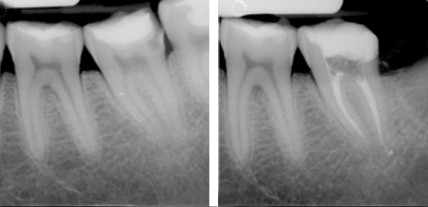

Fase diagnostica. Attraverso l'esame clinico obiettivo ed eventualmente strumentale-radiologico si determina la causa eziopatogenetica dell'avvenuta perdita di sostanza dentale e si stabilisce un corretto piano terapeutico.

Fase chirurgica. La riabilitazione morfo-funzionale dell'elemento dentario passa attraverso una prima fase chirurgica di rimozione meccanica e/o manuale del tessuto dentale infetto che viene effettuata anche con l'uso di rilevatori chimici di dentina patologica residua e rammollita (caries detectors). Questa seconda fase si conclude con la detersione della cavità con disinfettanti a base di clorexidina e/o altri prodotti merceologici bio-compatibili e con la medicazione interna della dentina e dei suoi tubuli dentinali (ossido di calcio, cementi vetro-jonomerici, liner, etc.) ove sono contenute le fibre del Tomes, delle estroflessioni nervose di origine neuro-pulpare, la cui esposizione ed il cui coinvolgimento (infiammatorio) causa sintomatologicamente il dolore e la sensibilità termica dei denti, come effetto della carie dentale.

Fase riabilitativa. Previo pre-trattamento dei tessuti dentali con tecnica "total etching" (mordenzatura) ed grazie anche all’uso di uno specifico sistema adesivo smalto-dentinale, infine, si procede alla ricostruzione dell'elemento dentale per apposizione stratificata di resine composite cromatiche, microibride e nano riempite, secondo una tecnica definita "incrementale". Infine, la verifica delle caratteristiche anatomiche, occluso-gnatologiche dei contatti inter-occlusali (con i denti antagonisti) e di quelle funzionali della ricostruzione appena eseguita, le conferiranno la reale dignità riabilitativa. L'ultimo atto ricostruttivo-riabilitativo della Terapia Conservativa è quello della lucidatura e brillantatura della riabilitazione dentale, che se è stato eseguito “lege artis”, garantirà esteticamente un validissimo effetto camaleontico e di “camoufflage”, nonché una valida bio-integrazione anatomica, funzionale, cromatica ed estetica con l’intero apparato masticatorio.